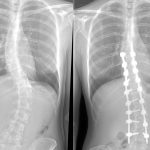

Сколиоз 4 степени

Самой тяжелой формой является сколиоз 4 степени (фото 5), когда искривление заметно окружающим. Лечение требует серьезных мер. Чаще всего сколиоз 4 степени исправляется только оперативным путем. У пациента, имеющего с-образный сколиоз, спина в буквальном смысле согнута в одну из сторон. Изгиб обычно более 50 градусов. 4 стадия сколиоза формируется при игнорировании лечения 3 стадии.

Правосторонний или левосторонний грудной сколиоз опасен тем, что меняется не только скелет, но и органы. Могут начаться проблемы с ЖКТ и легкими. Также имеется риск перехода в условный сколиоз 5 степени. Такого рода сколиоз у детей бывает редко. Взрослый человек наиболее подвержен этому виду.

В 4 стадии сколиоз шейного отдела позвоночника вместе с грудным и поясничным, представляют собой полностью искривленную спину в форме буквы S. Такие нарушения наблюдались вследствие внутренних изменений организма. К тому же, шейный сколиоз приводит к патологиям важных органов.